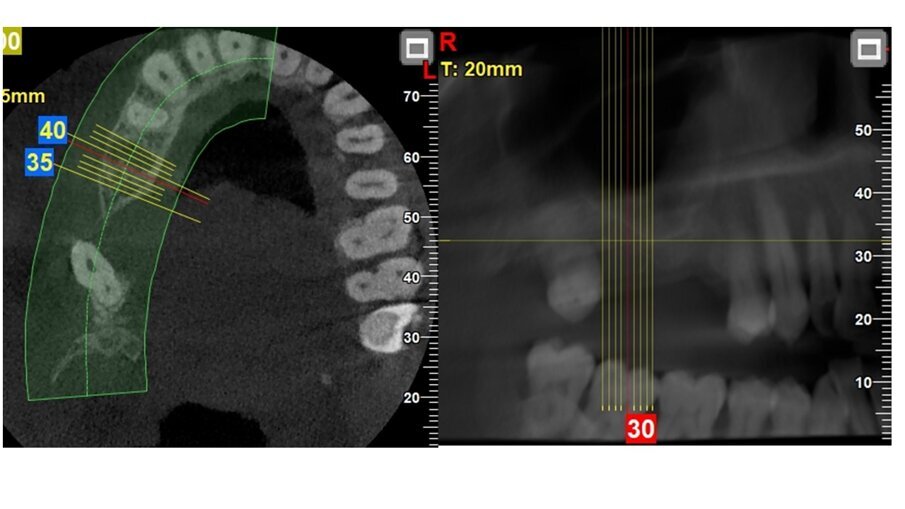

Una paziente donna di 63 anni, con osteoporosi ed ipotiroidismo, si presenta con assenza del 16 e 17, richiedendo riabilitazione dentale fissa. Si procede con l’esecuzione della CBCT per avere dettagli maggiori. Dall’analisi della CBCT nell’area edentula si misura un’altezza ossea verticale <5 mm in zona 16-17 e si nota la presenza di una lesione periapicale dell’elemento dentale 15 (Figg. 1-3). Quindi si programma l’intervento per l’estrazione del 15 e l’intervento per l’esecuzione del rialzo del seno mascellare con approccio laterale, con uso di osso bovino collagenato e spugnette di fibrina, al fine di ottenere l’incremento di osso verticale6. Dopo 5 mesi dall’esecuzione del rialzo di seno mascellare si esegue CBCT di controllo, per verificare l’effettivo aumento di osso verticale e programmare l’inserimento implantare (Figg. 4, 5).

A 5 mesi dall’intervento dal rialzo del seno mascellare con approccio laterale, grazie alla CBCT è stato possibile valutare la presenza di osso verticale. Si è visto che nell’area rigenerata si è avuto un incremento dell’osso, che presenta un range da 8 a 12 mm circa. Quindi verificata una rigenerazione verticale è possibile una riabilitazione implantare della zona 16, 17 e 15 con la scelta di impianti di lunghezza e un diametro adeguato (Figg. 4, 5)7, 8.